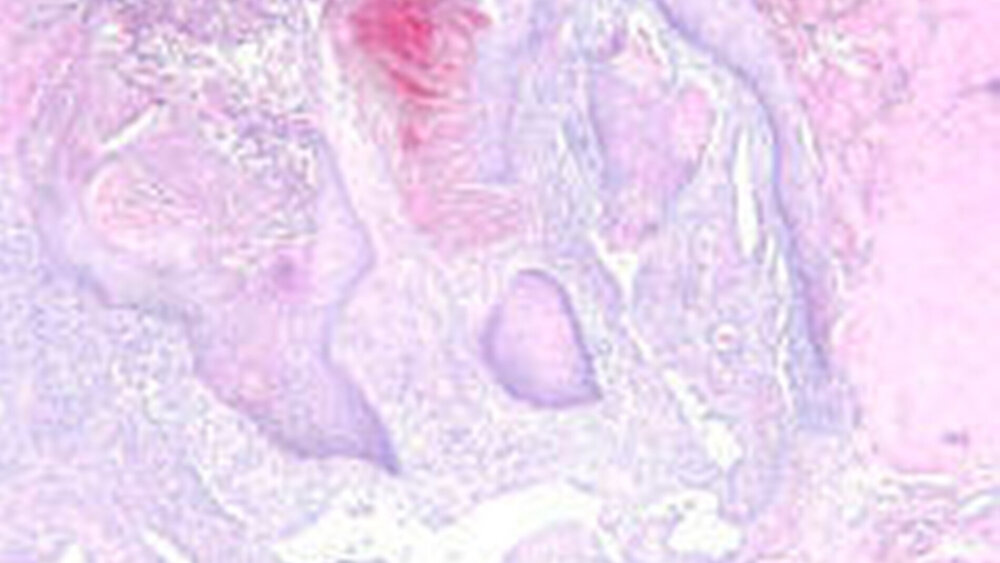

Der Tumor wurde ohne Sicherheitsabstand spindelförmig exzidiert (Abbildung 1a). Die histologischen Präparate zeigten ein oberflächlich gelegenes Schleimhautulkus mit granulozytärer Demarkation und Einblutungen. An den Rändern imponierte eine pseudoepitheliomatöse Hyperplasie mit ausgezogenen Epithelzapfen. Zur Tiefe hin fanden sich eine chronisch granulierende Entzündung sowie miteinander kommunizierende und endothelial ausgekleidete Gefäßspalten (Abbildungen 2a, 2b). Die histopathologische Begutachtung durch Dr. Stephan Schwarz, Institut für Pathologie der Universität Regensburg, diagnostizierte eine vollständig resezierte venöse Malformation.